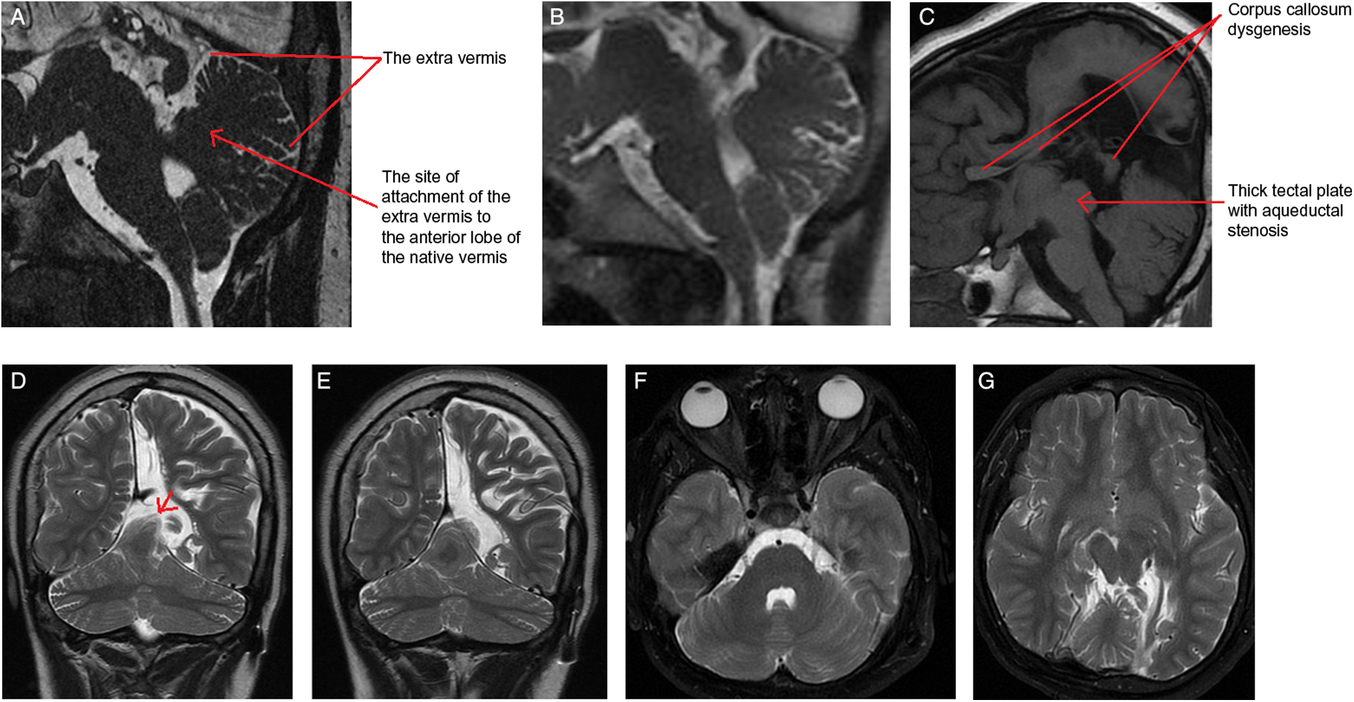

The MRI showed an extra-vermis attached to the anterior lobe of the native vermis, mainly to the culmen (Figure 1A,B). The anterior superior folia of this extra-cerebellar tissue herniate superiorly through the left side of the tentorial notch (Figure 1D,E). The extra-vermis has a primary fissure and a pre-pyramidal fissure. It demonstrates a similar signal intensity to the native one on all sequences (Figure 1C,F and G). Additionally, there is an aqueductal stenosis and corpus callosum dysgenesis (Figure 1C).Reference Hanna, Marsh and Swistun1

Figure 1: (A) Sagittal FIESTA image – slightly off midline – through the cerebellum demonstrates the extra vermis that is attached to the culmen of the native vermis. Notice the unique finding that the supernumerary vermis is developed from the dorsal aspect of the native vermis with a very clear site of attachment to the culmen and not from the brain stem. (B) Sagittal midline T2-weighted image shows the cerebellar vermian anomaly. (C) Sagittal T1-weighted MR image re-demonstrates the same findings, and shows the corpus callosum dysgenesis and the thick tectal plate with the resultant aqueductal stenosis. The anomalous vermis exhibits a similar signal intensity to the native one on coronal T2-weighted images (D and E). Coronal T2 weighted MRI images show the anomalous vermis herniated through the tentorium (red arrow in D). (F and G) Axial T2-weighted images show the normal morphology of the cerebellar hemispheres and re-demonstrate the extra vermis.